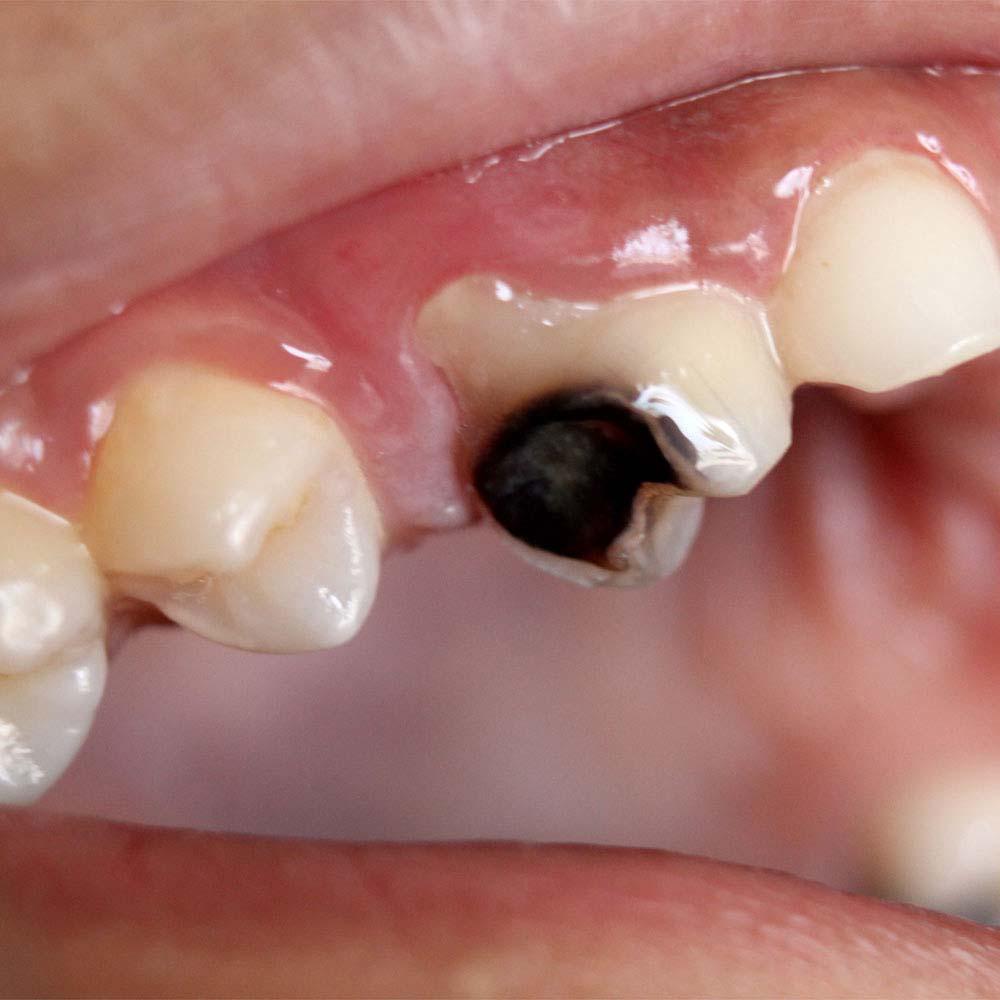

❺ 严重损坏的 牙齿

如果牙齿摔断的情况比较严重,比如牙冠大部分脱落,或者牙齿出现了松动、移位等情况,这时可能需要进行拔牙。

因为严重损坏的牙齿可能无法进行有效的修复,而且可能会影响到其他牙齿的健康和口腔的正常功能。